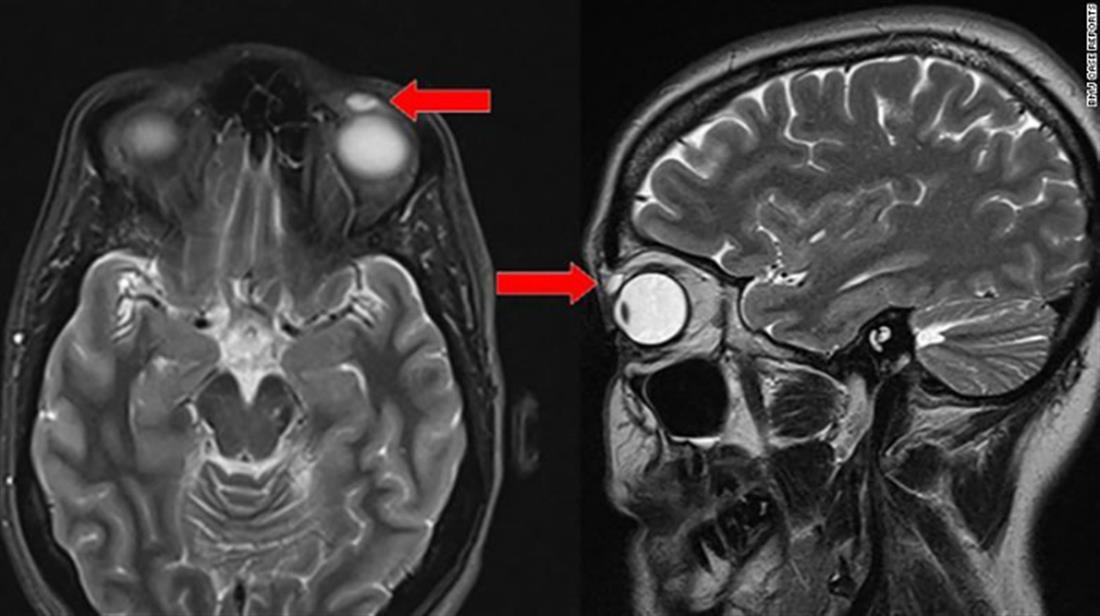

Σύμφωνα με αναφορά στο ιατρικό περιοδικό «BMJ Case Reports», ο οφθαλμίατρος ανακάλυψε μία κύστη έξι μηνών στο μάτι της γυναίκας και αμέσως προχώρησε στη διαδικασία αφαίρεσής της, κατά τη διάρκεια της οποίας ο φακός ράγισε και έσπασε.

Την απάντηση στο αίνιγμα για το πώς βρέθηκε ο φακός στο μάτι της, έδωσε η μητέρα της, η οποία θυμήθηκε ένα ατύχημα που είχε η κόρη της όταν έπαιζε μπάντμιντον πριν από 28 χρόνια.

Τότε, είχε χτυπηθεί στο αριστερό της μάτι και για ένα διάστημα φορούσε ημίσκληρους φακούς επαφής, ο ένας εκ των οποίων, όπως λανθασμένα θεωρούσαν οι γονείς της, είχε απλά πέσει και δεν είχε βρεθεί ποτέ.